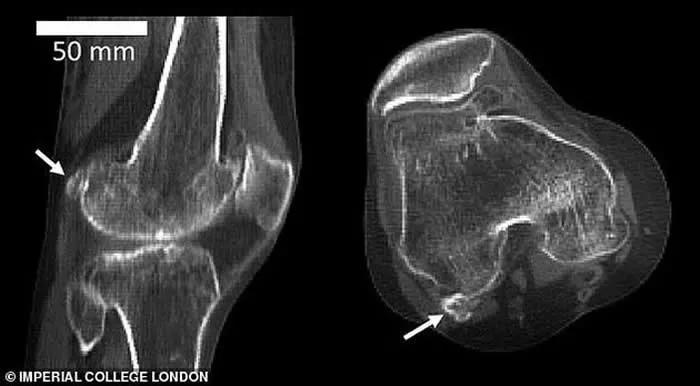

文章插图

它的直径不足1.3厘米 , 是在我们灵长类祖先身体上发现的 , 它被称为“骨骼阑尾” , 因为它的存在是毫无意义的 。 所以在古猿向人类发展的进程中 , 豆骨已经消失 。

然而研究人员分析了过去150多年进行的2.1万多项科学研究 , 发现目前豆骨在人体存在的概率是100年前的3倍 , 全球40%的人都长有豆骨 。

但是变得更高更重 , 膝盖承受的压力也会越来越大 , 为了更好承受压力 , 膝盖进化出来了新的骨骼 , 那就是豆骨 。 它会在未来逐渐成为人体解剖学中的一个正常变体 。

豆骨在一些哺乳动物之中仍然存在 , 它生长在肌肉的肌腱中 , 就像膝盖骨或髌骨一样 。 在哺乳动物之中 , 它可以帮助帮助减少肌腱内部的摩擦 , 改变肌肉力量 , 或者 , 就像膝盖骨一样 , 增加肌肉的机械力量 。

这对人类来说并不是好事情 , 出更多骨骼缓解压力 。 但是这将产生一个问题 , 膝骨骼会磨损重要的软骨组织 , 从而导致骨关节炎 。

豆骨还可能会造成膝盖受力不均 , 增大软骨损伤 。

它也可能在膝关节置换手术之后引发疼痛 , 因为多余的骨骼通过钻入大腿骨来保持其位置 , 当这部分骨骼被替换 , 将该骨骼移除后 , 骨骼位置将形成一个凹陷 , 当人们行走时 , 肌腱会从左至右产生“断裂感” , 出现疼痛 。

研究人员在调查中发现 , 在进行膝关节置换手术之后 , 有些病人切除了豆骨 , 而另一些病人却留下了 。 术后出现疼痛和麻痹仅见于仍有豆骨的患者 。 因此 , 科学家建议在进行膝关节置换手术时移除豆骨 。

不过 , 豆骨它的存在可能并不总是被X光或CT扫描所发现 。 例如 , 一项针对中国人群的研究报告说 , 57.9%的豆骨在X光片上看不到 。